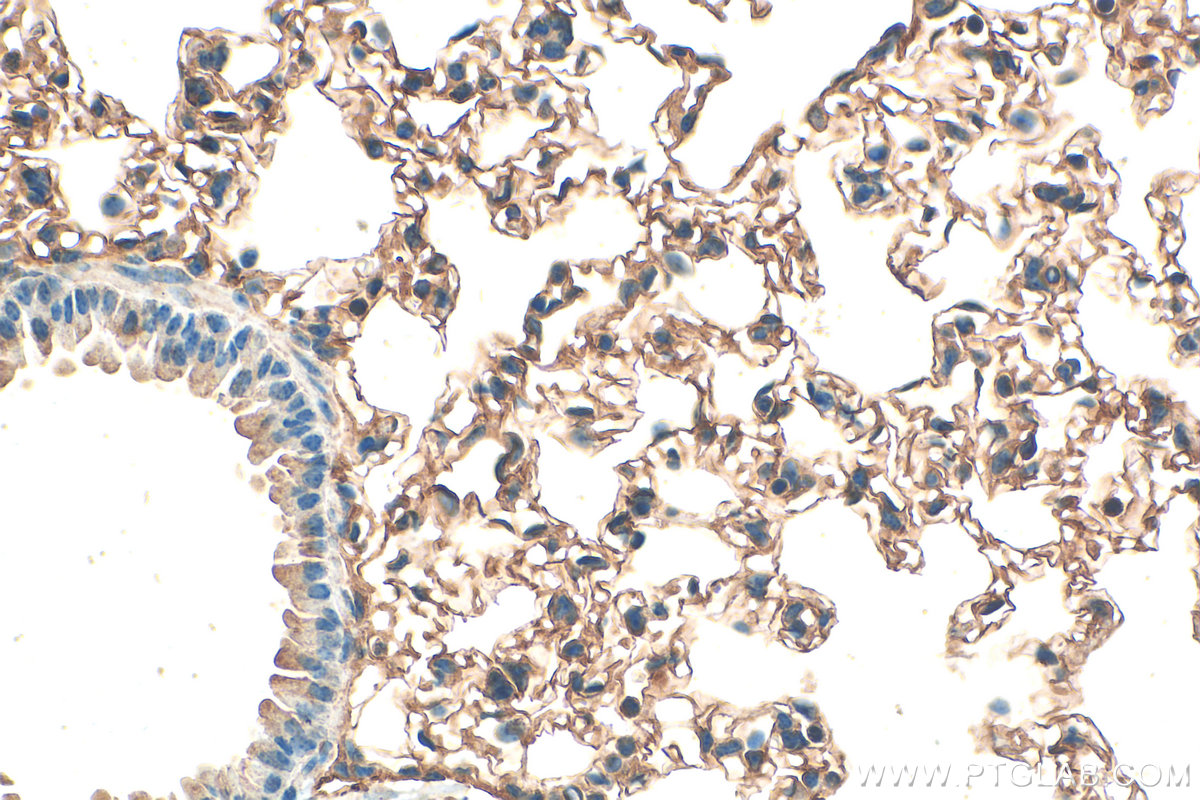

| Positive IHC detected in | human lung tissue, human brain tissue, mouse brain tissue, mouse lung tissue Note: suggested antigen retrieval with TE buffer pH 9.0; (*) Alternatively, antigen retrieval may be performed with citrate buffer pH 6.0 |

| Immunohistochemistry (IHC) | IHC : 1:50-1:500 |